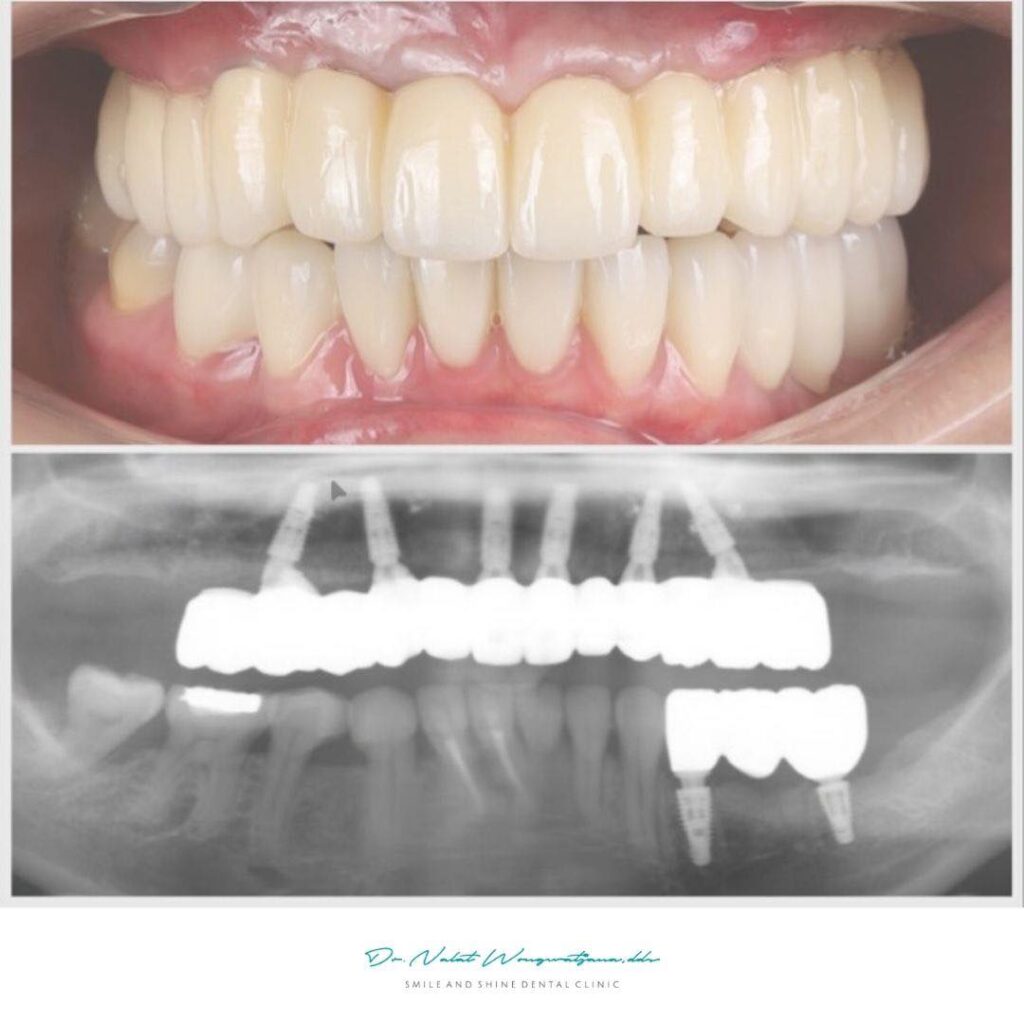

Before & After

การทำ รากฟันเทียม All-on-6 แบบ FP1 คือการใช้รากฟันเทียม 6 ตัวรองรับฟันทั้งขากรรไกร โดยออกแบบให้ฟันโผล่ออกจากเหงือกจริงเหมือนฟันธรรมชาติ ไม่ใช้เหงือกปลอม เทคนิคนี้มักใช้ร่วมกับ Digital Guided Surgery เพื่อวางตำแหน่งรากเทียมอย่างแม่นยำและสามารถใส่ฟันชั่วคราวได้ทันที

All-on-6 เป็นเทคนิคการใช้ รากฟันเทียม 6 ตัวรองรับฟันทั้งขากรรไกร เหมาะกับผู้ที่สูญเสียฟันจำนวนมาก ส่วน FP1 (Fixed Prosthesis 1) คือการออกแบบฟันให้ดูเหมือนฟันธรรมชาติ โดยฟันโผล่ออกจากเหงือกจริงโดยไม่มีเหงือกปลอม ทำให้ดูเป็นธรรมชาติที่สุดทั้งในด้านความสวยงามและการใช้งาน

- สะพานฟันบนรากเทียมแบบ FP1

- วีเนียร์ฟันล่าง

- ครอบฟันเซรามิก